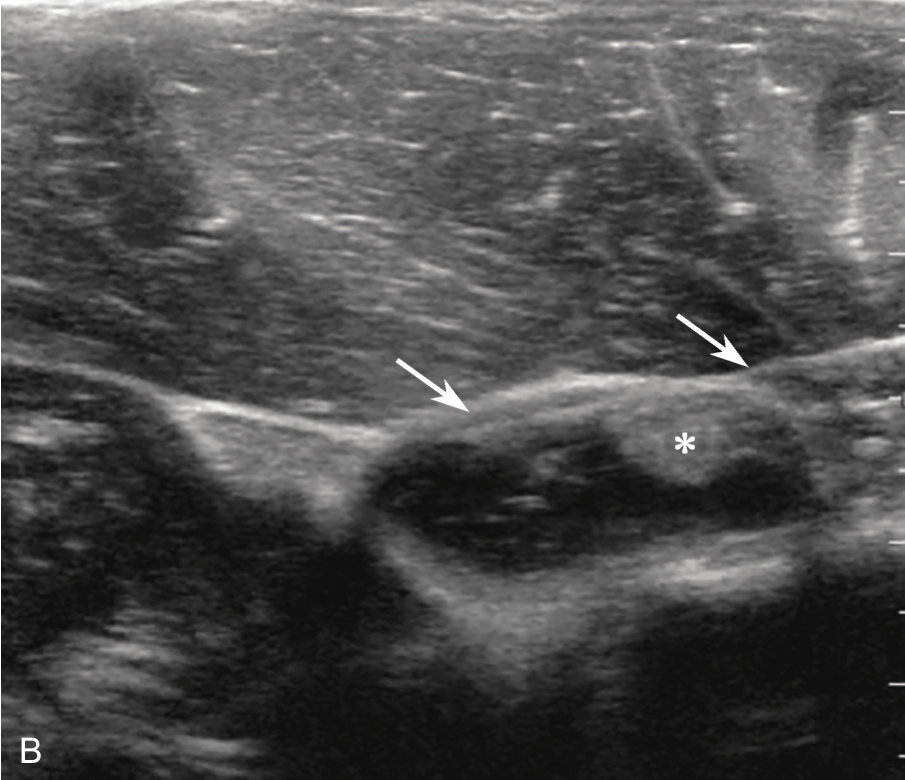

▲ 图2-3-5 超声引导下肱二头肌长头腱鞘介入治疗超声图(二)

A、B.超声引导下平面内进针法,针尖进入腱鞘内;箭头:穿刺针;星号:肌腱